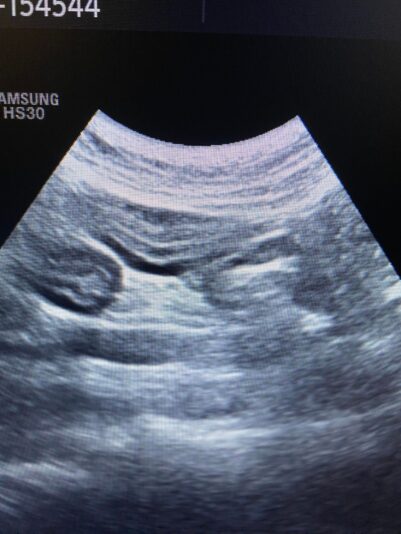

these are the photos of the bloodwork and from the ultrasound

Hi Geert and the whole team,

This post is about a patient of mine that came to me on Wednesday.

General information and history: Cat, male, not castrated, 11 years old with different behaviour since 3 days. According with the owners, the cat didnt want to eat and drink for 3 days. Also he wasnt active and he was hiding. The owners didnt have…